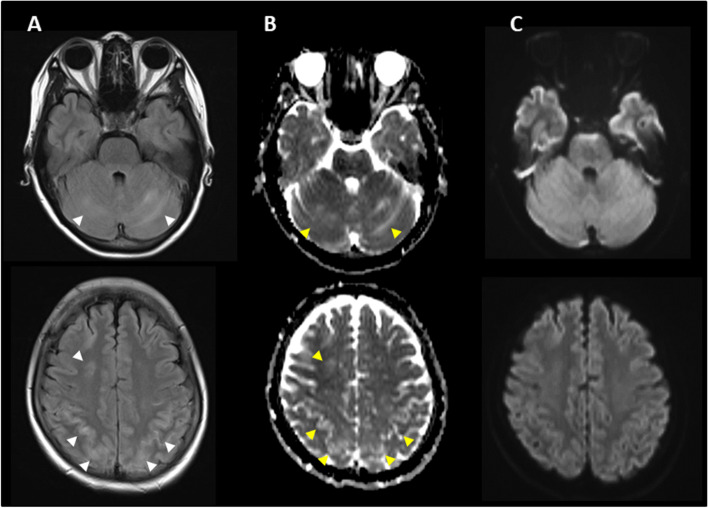

Five days after onset, brain MRI showed regions of hyperintensity in the right frontal lobe, bilateral parietal cortex and subcortex, and bilateral cerebellar lobes on FLAIR images (Fig. 1A). In addition, although the apparent diffusion coefficient (ADC) map showed elevations (Fig. 1B), no region of hyperintensity was observed on the diffusion-weighted image (DWI), suggesting angioedema (Fig. 1C). No abnormal findings were observed on brain magnetic resonance angiography (MRA) at the time of onset of the first headache (Fig. 2A). However, four days after the onset, multiple cerebrovascular spasms were observed, in which alternate contractions and dilations of several main arteries occurred (Fig. 2B). On the electrocardiogram (ECG) five days after the onset of the first headache, ST depression was observed in limb leads II, III, and aVF, and in the chest leads V3 to V6 (Fig. 3A). Ultrasound cardiography (UCG) showed a hypokinesis at the base of the side of intraventricular septum, with a slight decrease in ejection fraction (EF = 51.6%) and in fractional shortening (FS = 25.9%) (Fig. 4A). Although no symptoms of angina were observed 5 days after onset of first headache, left ventricular hypofunction leading to impending heart failure was suspected. Therefore, a calcium channel blocker and a nitrate were administered.

Based on her clinical course and imaging findings, she was diagnosed with reversible cerebral vasoconstriction syndrome (RCVS) with cardiac involvement. We administered 5 mg of the calcium channel blocker amlodipine besylate, 25 mg of nitroglycerin, and 500 mg of the antiepileptic drug levetiracetam. The hyperintense regions on FLAIR images completely disappeared 23 days after onset of first headache. She showed no exacerbation of heart failure, and the ECG (Fig. 3B) and UCG (Fig. 4B) findings were found to be normal eight days after onset of first headache. To avoid the risk of vascular spasm by iodinated contrast medium, we did not perform cardiac catheterization or coronary computed tomography (CT)-angiography until her RCVS was fully controlled. Since no recurrence of symptoms was observed after the treatment, we performed coronary CT-angiography seven months after the onset, which showed no significant vasoconstriction in any coronary artery (Fig. 5A, B).